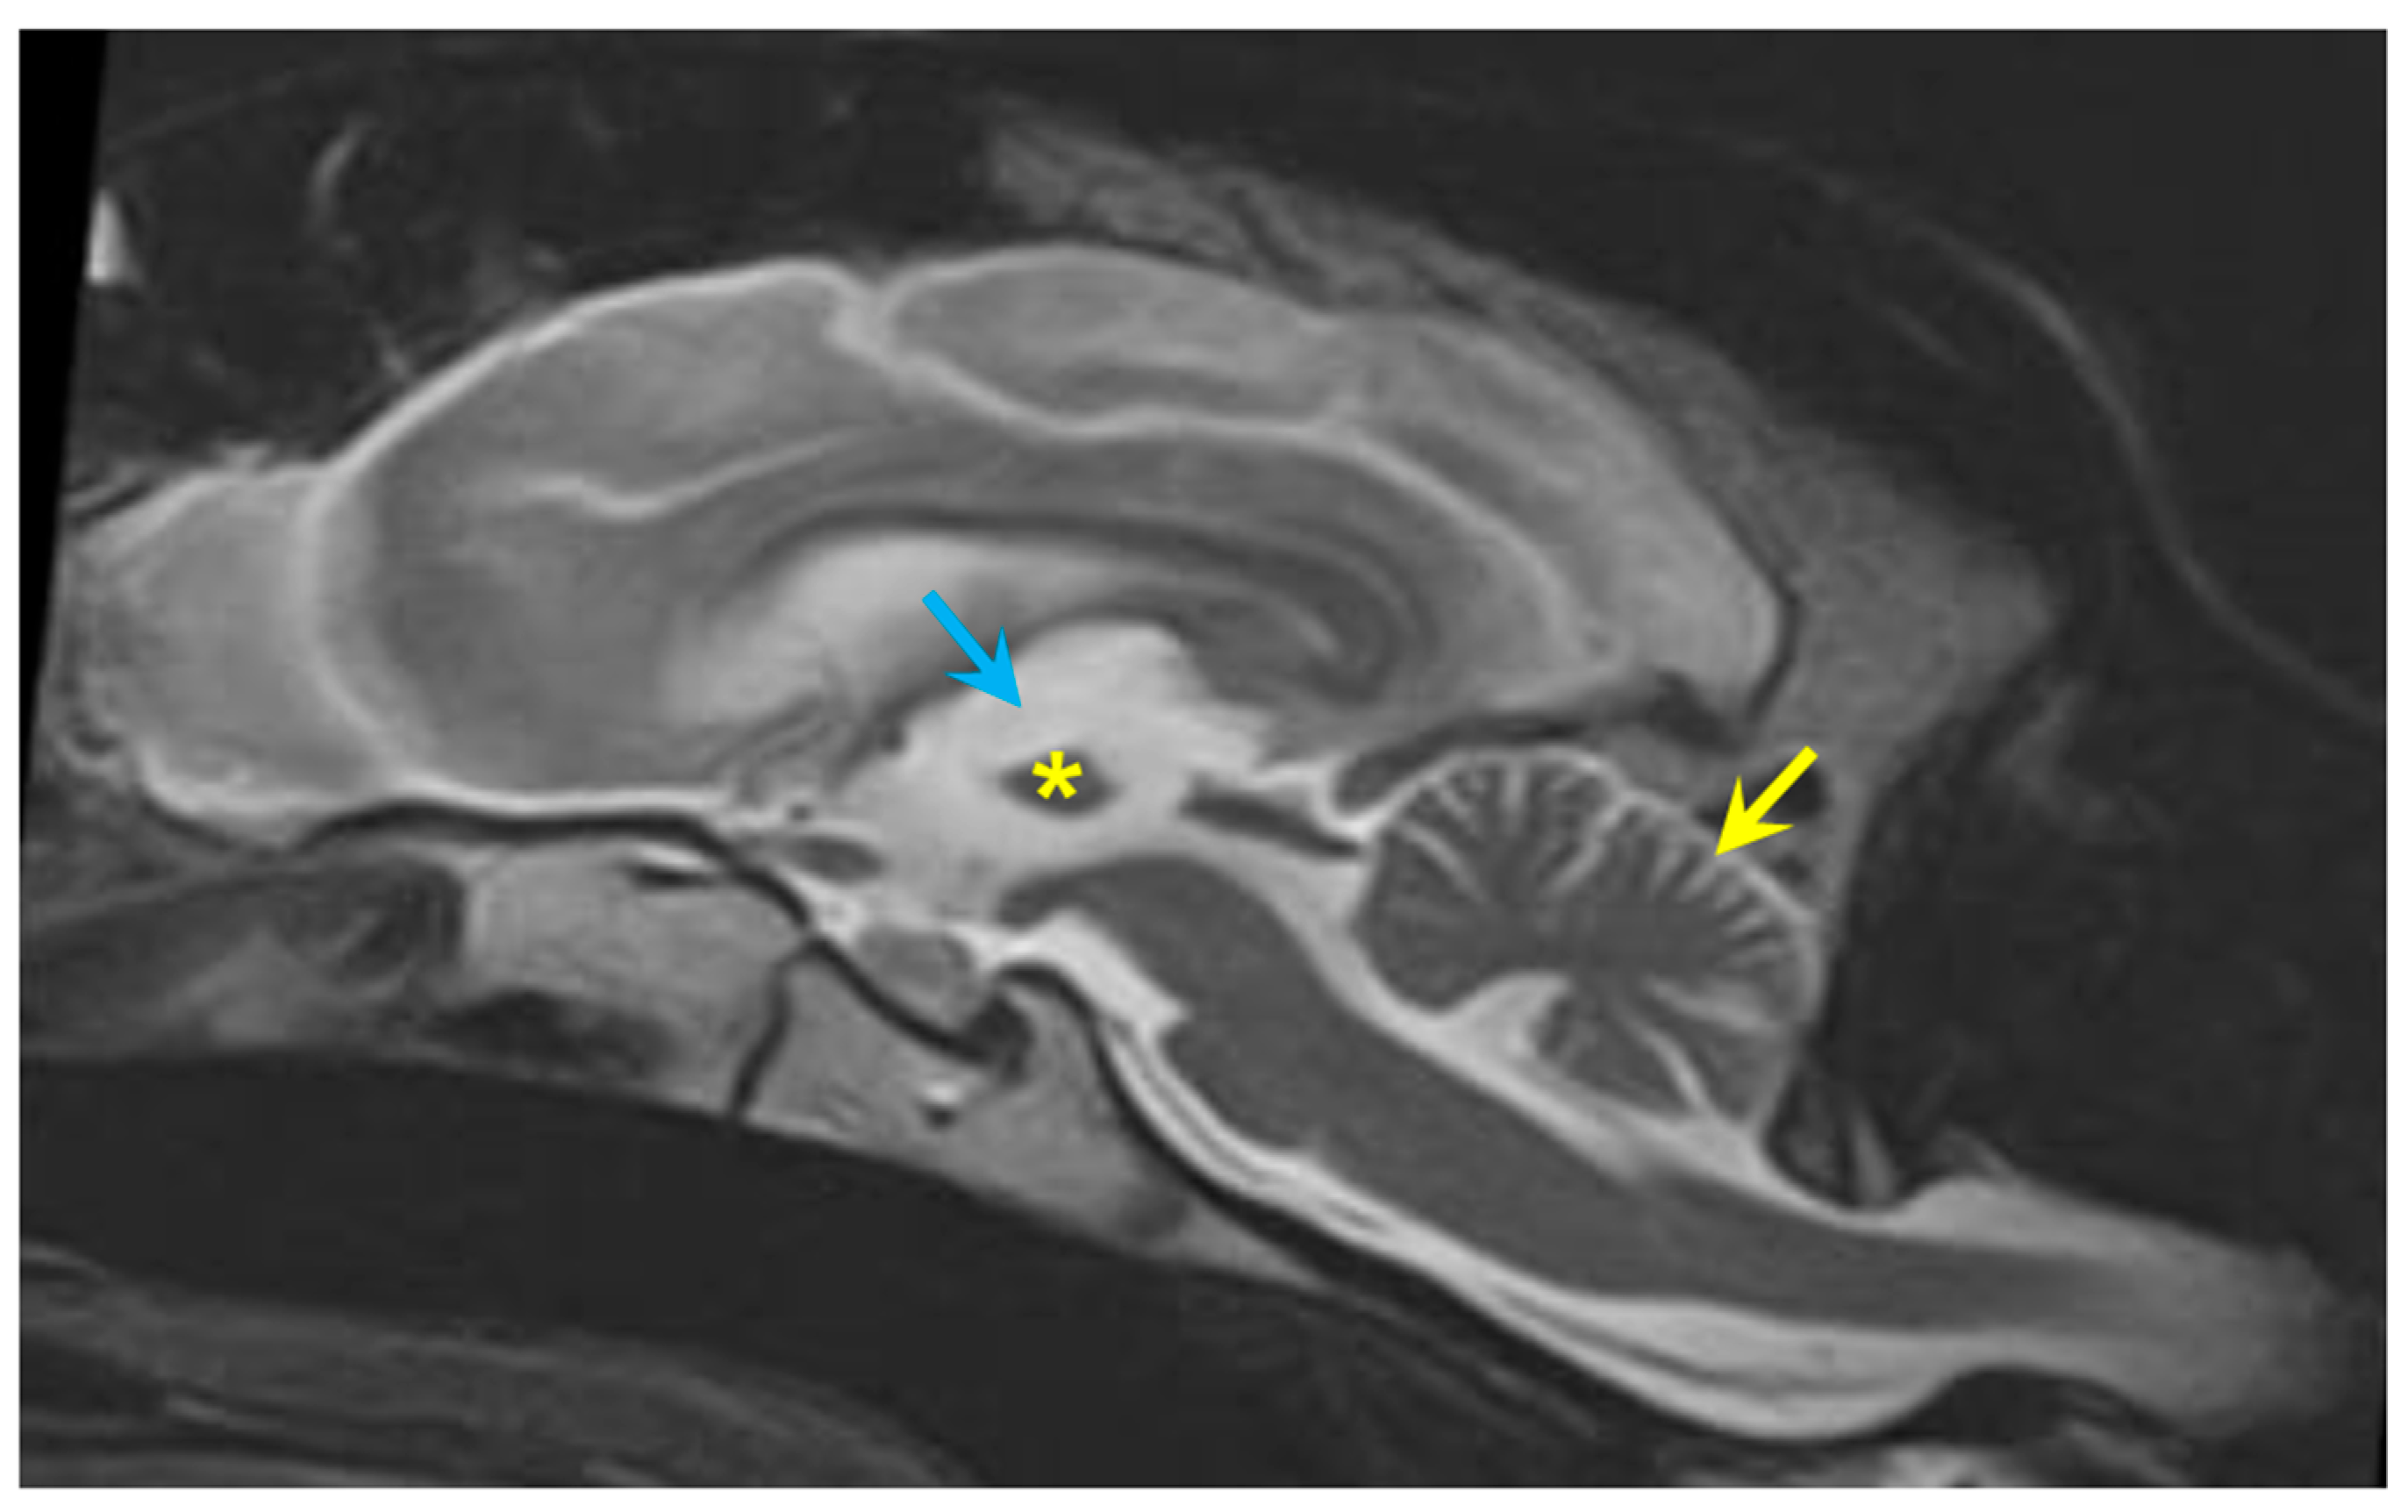

3.1. Disease Phenotype

3.2. Microscopic Findings